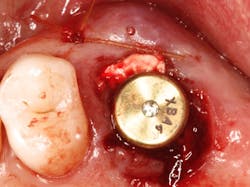

The authors noted a paradigm shift in their practices over the last several years. Hattingh et al. published a technique article regarding immediate placement of ultrawide diameter implants in molar sockets.14 Instead of the more traditional protocol that involved diagnosis of a nonrestorable molar with subsequent extraction, graft, osseous healing, implant placement, osseointegration, and implant restoration, the authors adopted an accelerated treatment protocol due to the availability of site-specific implants.

Site-specific implants for specific and varied implant surgical and prosthetic therapies allow clinicians’ choices regarding precisely designed products for individual clinical applications. These implants have been developed to provide improved primary stability, avoid/minimize preimplant bone grafting procedures, and allow for improved soft- and hard-tissue preservation around implants.4,5 Site-specific implants can also accelerate treatment by placing specific implants directly into extraction sockets immediately after tooth removal. Furthermore, if primary stability is optimized, site-specific implants can be loaded sooner, which usually leads to fewer patient visits, better soft-tissue profiles, and quicker overall treatment.5-9